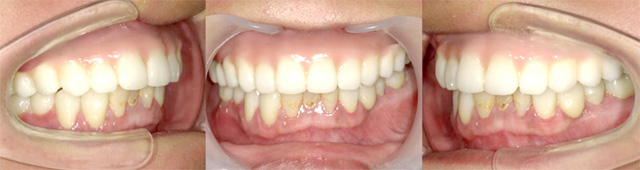

オールオン4の治療例:2

治療前

治療後